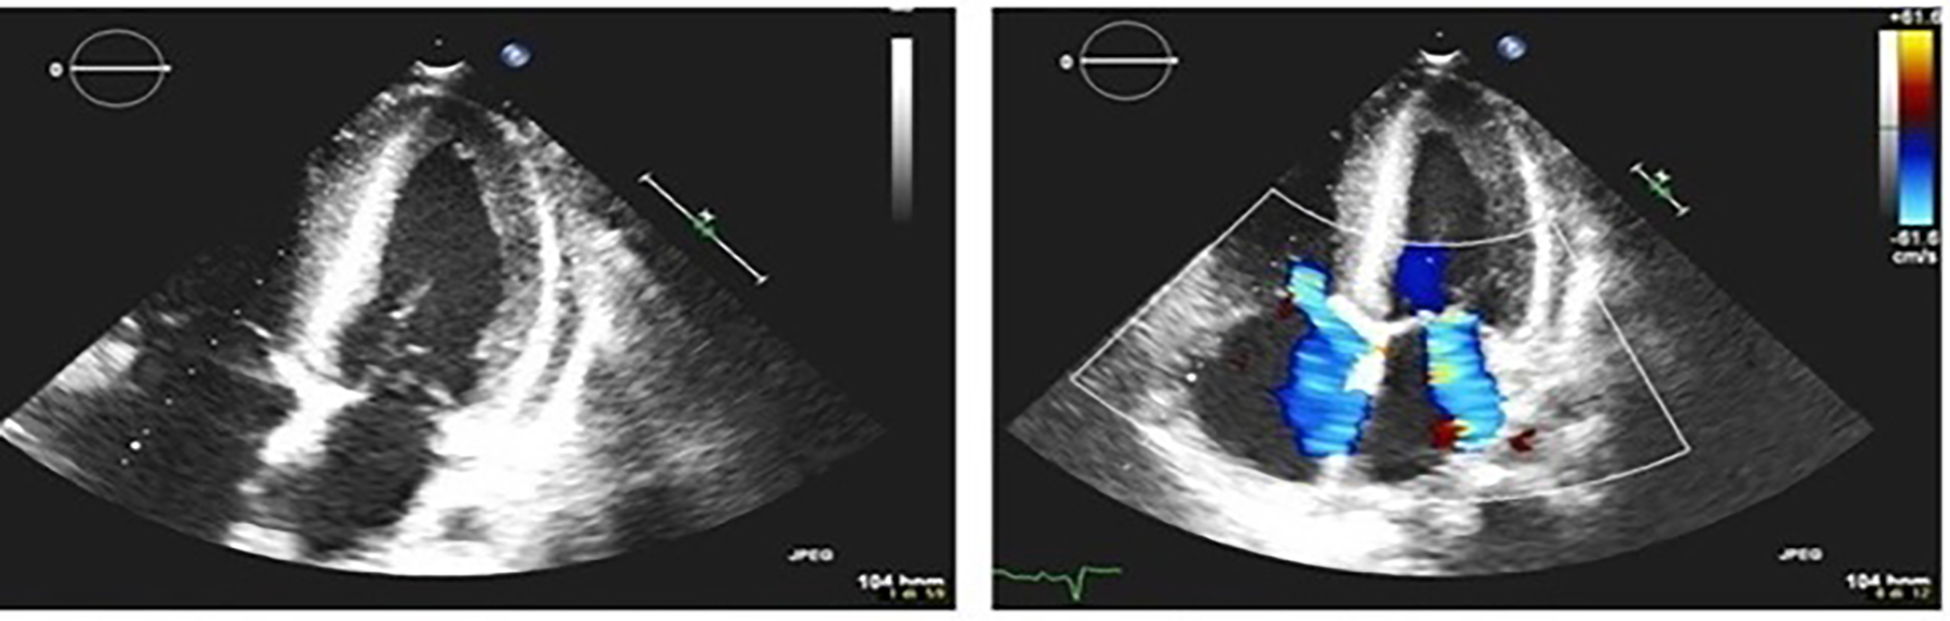

The patient was a 17-year-old boy who was previously diagnosed with a severe congenital heart disease. At 10 years of age, the patient was listed for heart transplantation and at 12 years underwent heart transplantation. At 16 years of age, the patient was diagnosed with stage 3B Hodgkin's lymphoma post-transplant lymphoproliferative disorder (HL-PTLD) associated with an Epstein–Barr virus (EBV) infection. It is an uncommon PTLD with an unclear prognosis; however, treatment with HL-specific chemotherapy is associated with improved overall survival and event-free survival. The patient received combination chemotherapy with brentuximab vedotin (an anti-CD30 monoclonal antibody) and doxorubicin, vinblastine, and dacarbazinein (BV–AVD). The doses of BV, doxorubicin, vinblastine, and dacarbazinein were 1.2 mg/kg, 25 mg/m2, 6 mg/m2, and 375 mg/m2 (once per day on days 1 and 15), respectively. During the treatment, the mycophenolate mofetile; course was interrupted. Positron Emission Tomography after 2 cycles of BV-AVD revealed a complete metabolic response; the patient received a total of 4 cycles that were well tolerated. No cardiac toxicity was observed during the treatment. At the end of the treatment, disease assessment confirmed a complete metabolic response, and EBV was not detected in the blood. However, 1 month after the last chemotherapy cycle, i.e., at 17 years of age, the patient was admitted to the intensive care unit with symptoms and hemodynamic signs of a cardiogenic shock. Three days prior to this, he had experienced a mild increase in the body temperature (37.5°C) along with decreased energy and poor appetite. Laboratory testing revealed a normal blood cell count with no increase in eosinophils and abnormal cells; furthermore, the C-reactive protein level was normal as well. Troponin I level (3,408.3 pg/ml; high-sensitivity troponin assay) and brain natriuretic peptide level (3,890.1 pg/ml) were clearly elevated, with the creatinine level, EBV CRP copy number, and everolimus level being 1.88 mg/dl, 23,793 copies/ml, and 5 μg/L, respectively. A 12-lead electrocardiogram revealed sinus tachycardia with widespread ST depression. A chest radiograph (Figure 1) revealed bilateral pleural effusion, while a 2D-echocardiogram revealed severe left ventricular dysfunction (ejection fraction: 20%). An altered diastolic function and moderate mitral regurgitation were noted, and a thickening of the myocardium that can be evocative of eosinophilic infiltration (Figure 2). The right ventricular function was also impaired (right ventricular fractional area change, 20%; tricuspid annular plane systolic excursion, 12 mm) with severe tricuspid regurgitation and elevated right ventricular pressure. Thin layers of pericardial effusion and moderate bilateral pleural effusion were also noted. Therapy for acute heart failure was initiated intravenously using inotropic drugs (milrinone, adrenaline, vasopressin, and levosimendan); their doses were determined using an internal protocol. The patient underwent cardiac catheterization, coronarography, and endomyocardial biopsy (EMB) of the right ventricle. Coronarography was negative for obstructive lesions, and no intravascular ultrasound was performed at this time; however, the most recent study revealed a Stanford II coronary artery vasculopathy. Owing to the rapidly worsening hemodynamic stability, arteriovenous extracorporeal membrane oxygenation (ECMO) was initiated. During ECMO, the clinical conditions were critical but more stable.

Figure 2

2D-echocardiogram shows moderate mitral regurgitation and thickening of the myocardium.